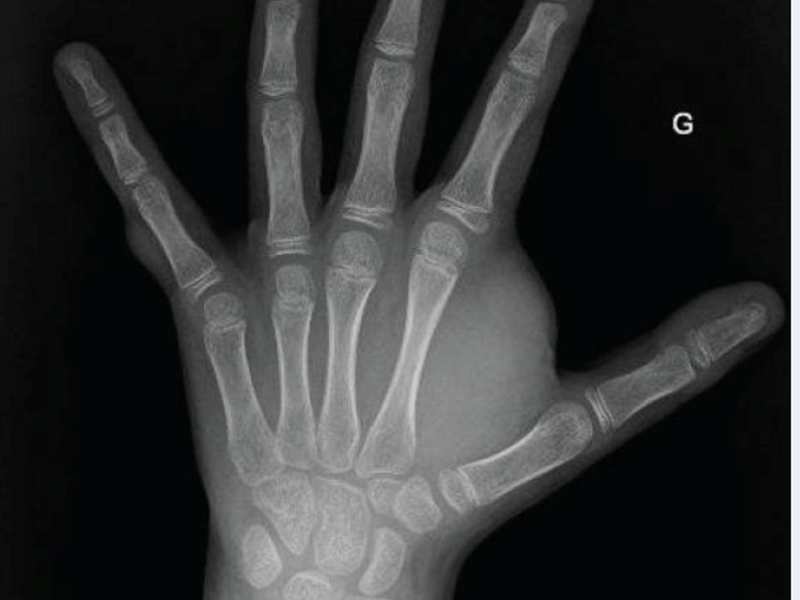

Subcutaneous neurofibroma (left hand): X-ray and photograph

A study by French researchers reported in ecancermedicalscience, showed dramatic results in a 12-year-old boy with NF1, who was finding walking impossible, and suffering increased pain in his hand (see images on the right). Within a week of beginning treatment with a MEK Inhibitor, Trametinib, he was walking again, and the pain had disappeared. These results were sustained, and after a year, he no longer needed to take the drug.